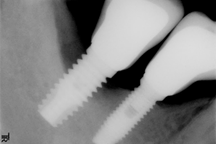

Moderate: Probing depth >6 mm, with bleeding and/or suppuration in >2 implant sites, and bone loss between 25% and 50% of the total implant length (Fig. 3)

Advanced: Probing depth >8 mm, with bleeding and/or suppuration in >2 implant sites, and bone loss >50% of the total implant length (Fig. 4)